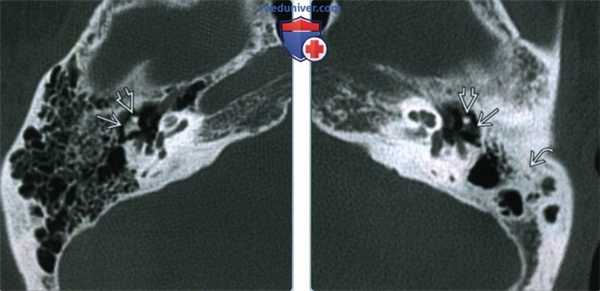

(Слева) При аксиальной КТ в костном окне визуализируется нормальный короткий отросток наковальни справа и головка молоточка. Обратите внимание на хорошо пневматизированный сосцевидный отросток.

(Справа) При аксиальной КТ левой височной кости у пациента с хроническим средним отитом в анамнезе определяется деоссификация короткого отростка наковальни слева. Головка молоточка по размерам и плотности не изменена. Пневматизация сосцевидного отростка снижена вследствие отомастоидита во время его формирования.